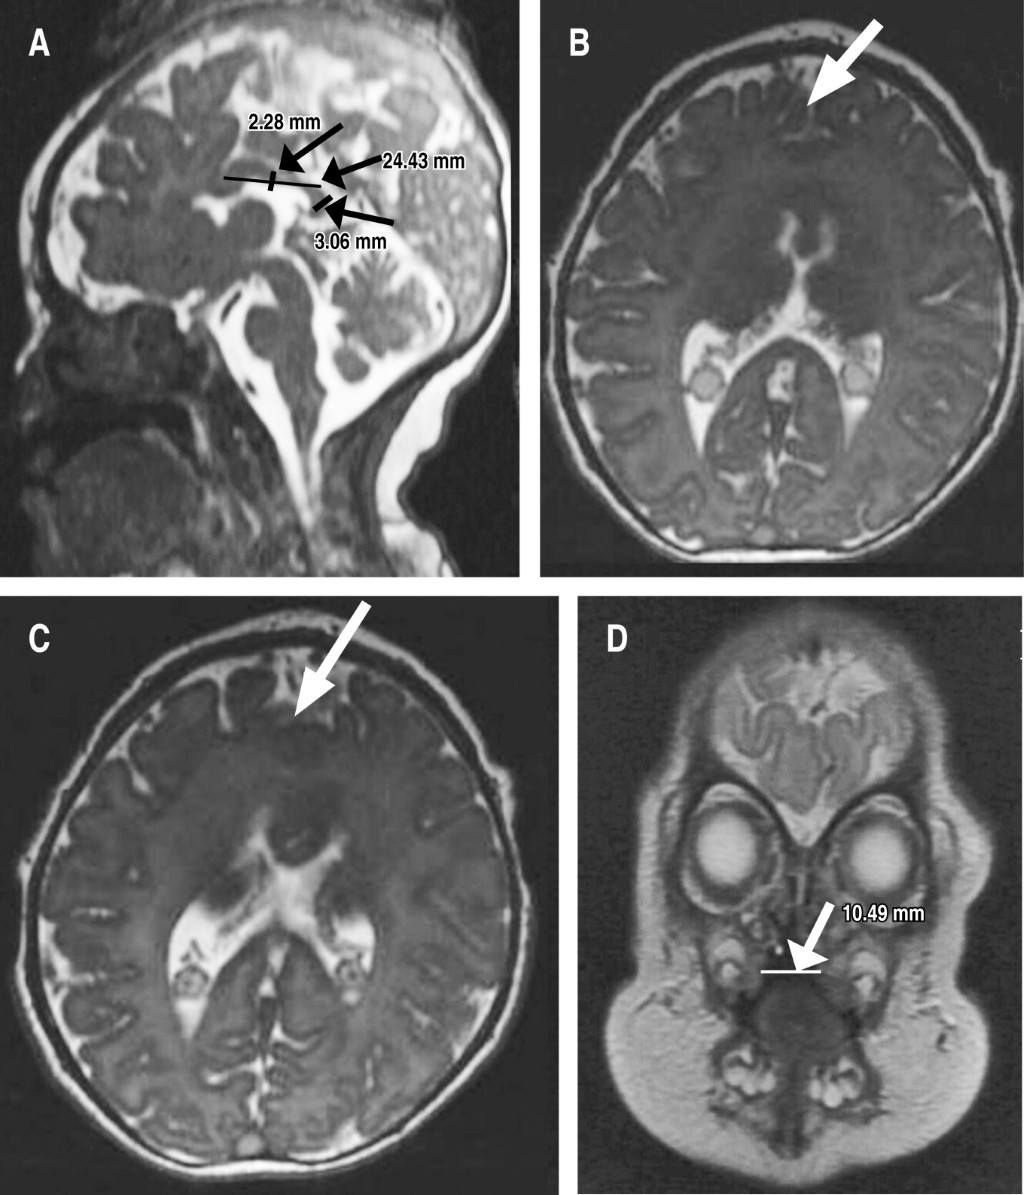

Debido al diagnóstico de HPE, inmediatamente posterior a su nacimiento se tomaron imágenes de resonancia magnética, que revelaron anomalías de la línea media caracterizadas por fusión interhemisférica parcial de los lóbulos frontales, asociada con la ausencia de la rodilla del cuerpo calloso, que tiene una longitud de 24.4 mm, cuerpo de 2.3 mm y esplenio de 3.1 mm, condicionando disminución de la amplitud de los huecos frontales, pero con núcleos grises conservados (Figura 1).

Figura 1